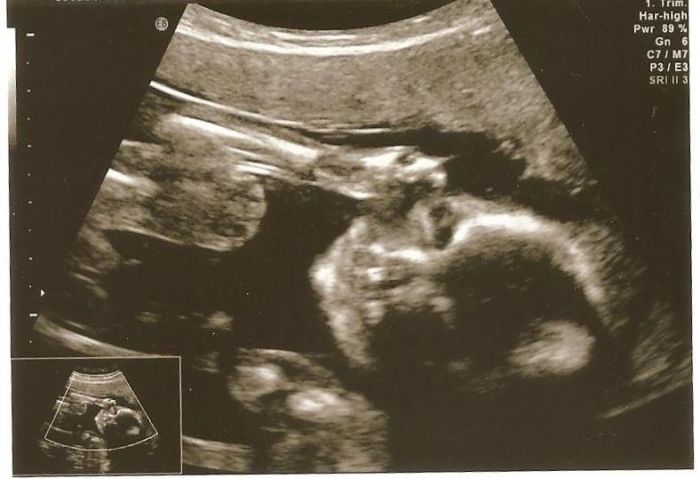

No doktor mi v tom sedmém týdnu udělal vnitřní ultrazvuk a ptal se mě, jestli tam něco vidím. A já na to: vidím bílý a tmavý flek

No ten tmavý flek byl ten náš maličký vetřelec

první foto z ultrazvuku mám až z 12.tt, pak z 13.tt a poslední z 20.tt - to posílám